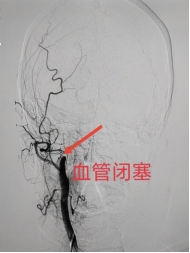

急性颅内动脉取栓!这是一项尖端的微创介入治疗方法,王主任团队先是为王女士先进行了全脑血管造影,精准捕捉到了右侧颈内动脉闭塞部位(图2-3),随后急诊进行颅内动脉取栓术,抽吸出暗红色血栓多块(图4),随着这些潜藏在王女士脑袋中的“头号杀手”被完全取出,这部分血管终于完全再通(图5),王女士左侧肢体肌力即刻恢复正常(图6)。